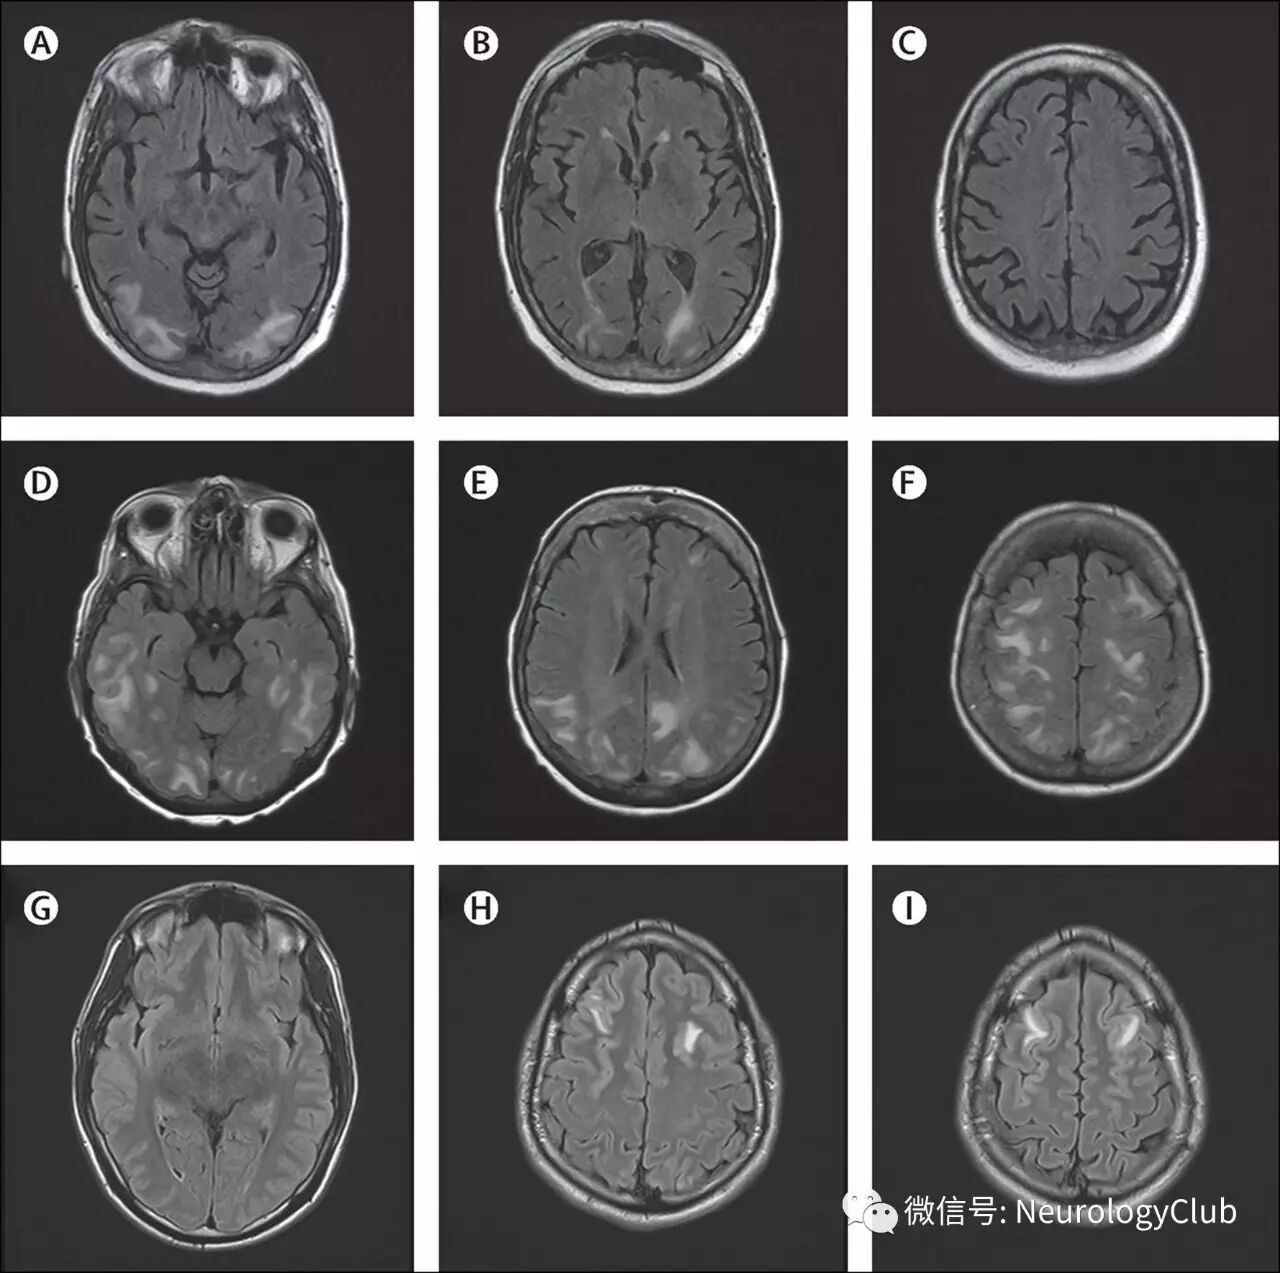

颅脑影像学有助于诊断PRES以及鉴别诊断。血管源性水肿可以通过CT来发现,但颅脑MRI更敏感。由于缺乏诊断金标准,无法评估MRI的特异性。颅脑MRI典型表现为双侧顶枕叶为主的血管源性水肿,呈T1低信号,T2/FLAIR高信号,DWI等或低信号,ADC高信号。通常累及皮质下白质,较少累及皮质。水肿几乎累及双侧,不完全对称。

(图2:典型的黑水像PRES影像学表现)

影像学表现可分为四型:顶枕型,全脑分水岭型,额上回型和中央变异型。影像学分型和水肿严重程度都不与临床表现分型和严重程度相关。额叶和颞叶受累者约占75%。累及基底节和脑干者有1/3,累及小脑者约占半数。这些部位的水肿一般是伴随着顶枕部位的受累。病变不累及顶枕区域者少见。仅累及单侧大脑和孤立性脑干与小脑水肿者需要排除其它疾病。

(图3:均为黑水像;A-C:顶枕型PRES;D-F:全脑分水岭型PRES;G-I:额上回型PRES)